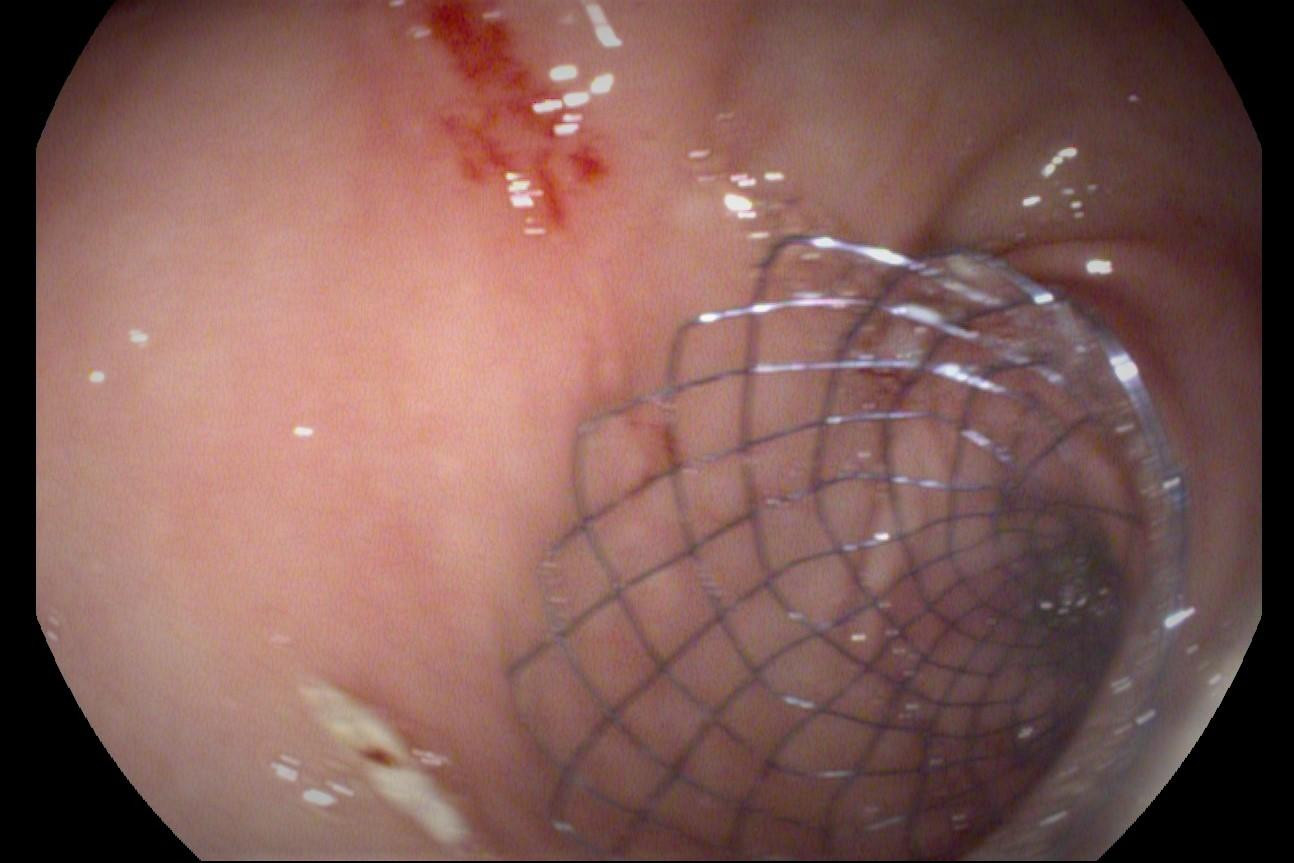

Sau hội chẩn, các bác sĩ đã quyết định nội soi đặt stent kim loại tá tràng dài 9cm, đường kính 22mm, từ môn vị đến tá tràng, khai thông đường ruột bị tắc cho bệnh nhân. Sau can thiệp, bệnh nhân hết đau bụng, hết ói, ăn được thức ăn mềm, sức khỏe đang dần bình phục.

![]() |

| Stent là giá đỡ dạng khung kim loại được đặt thành công vào lòng ruột, khai thông vị trí tắc nghẽn cho bệnh nhân |